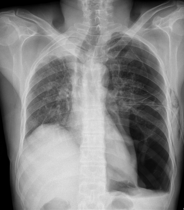

âȘ Table 5: We visualize samples of the generated reports for three cases. We bold the identical descriptions, underline the additional identified findings, and in red the failure findings..

X-ray Image | Baseline | M2TR | R2Gen | Ours |

![]() |

Pneumothorax gauche de grande abondance./OpacitĂ© rĂ©ticulo-micronodulaire avec verre dĂ©poli de lâhĂ©michamp pulmonaire gauche avec individualisation dâune volumineuse bulle apical gauche./ | Pneumothorax droit de grande abondance./ OpacitĂ© rĂ©ticulo-micronodulaire dans lâhĂ©michamp pulmonaire droit, avec verre dĂ©poli et prĂ©sence d'une bulle apicale droite importante./ | Pneumothorax gauche modĂ©rĂ©./ OpacitĂ©s rĂ©ticulo-micronodulaires avec zones de verre dĂ©poli Ă©tendues sur lâhĂ©michamp pulmonaire droit./ | Pneumothorax bilatĂ©ral de grande abondance./ PrĂ©sence d'opacitĂ© rĂ©ticulo-micronodulaire avec aspect de verre dĂ©poli sur les deux hĂ©michamps pulmonaires, plus de grande bulle apicale sur le cĂŽtĂ© gauche./ SurĂ©levation de la coupole diaphragmatique droite avec trachĂ©e tirĂ©e vers la droite./ |